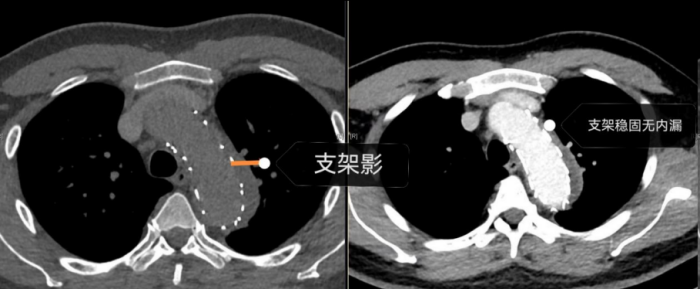

手术室内,患者血压一度飙至惊人的320/150mmHg,循环濒临崩溃!麻醉团队全力稳定循环。在患者下肢几乎无法触摸到脉搏的极端条件下,外周血管介入科主任赵扬程及团队迎难而上,凭借精湛技术,精准置入支架,成功封堵主动脉内膜巨大破口,并精细重建了主动脉弓部受累的重要分支血管,恢复关键血流。这场持续近3小时的手术每一步都高风险且高度紧张,如同在死神面前进行“拆弹”。最终,这颗“血管炸弹”被成功拆除。